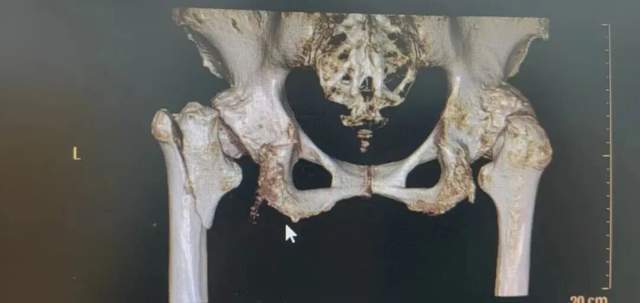

图片

(▲术后X片检查)